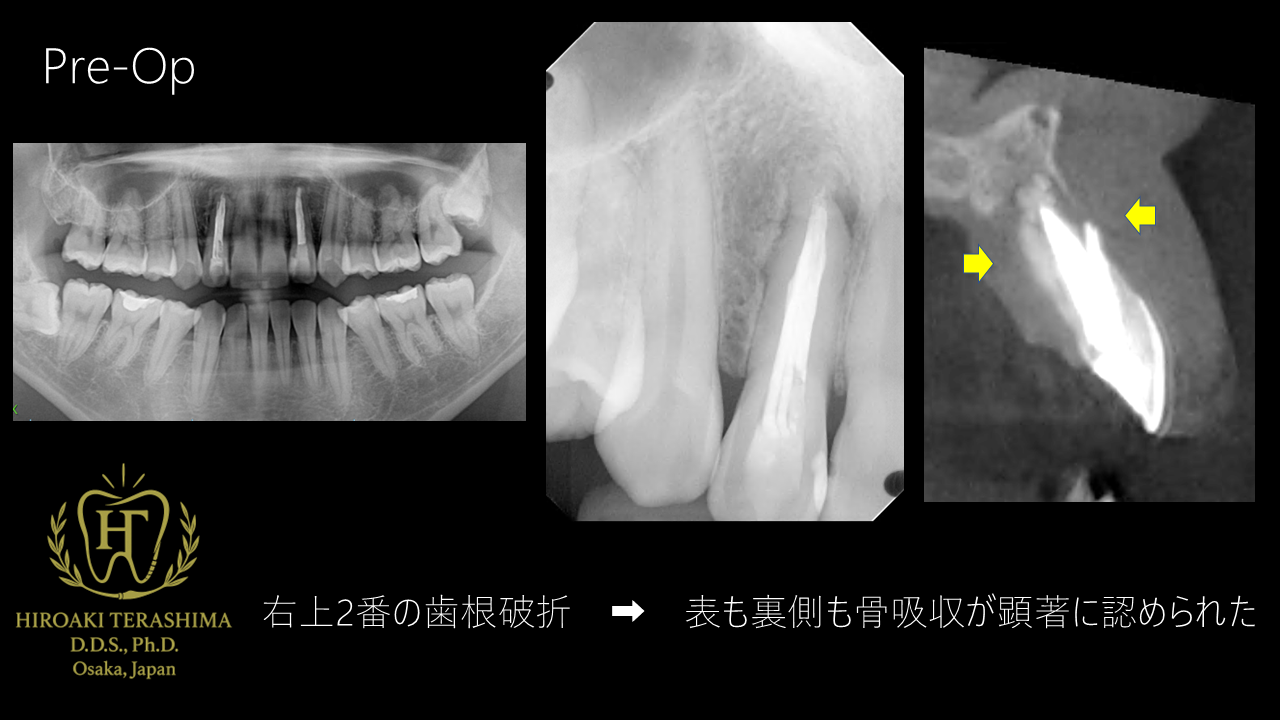

右上2番 歯根破折(腫脹・瘻孔あり)

唇側・口蓋側ともに根尖付近まで骨吸収

-

抜歯は不可避

審美領域であるため、抜歯即時埋入が必須と診断